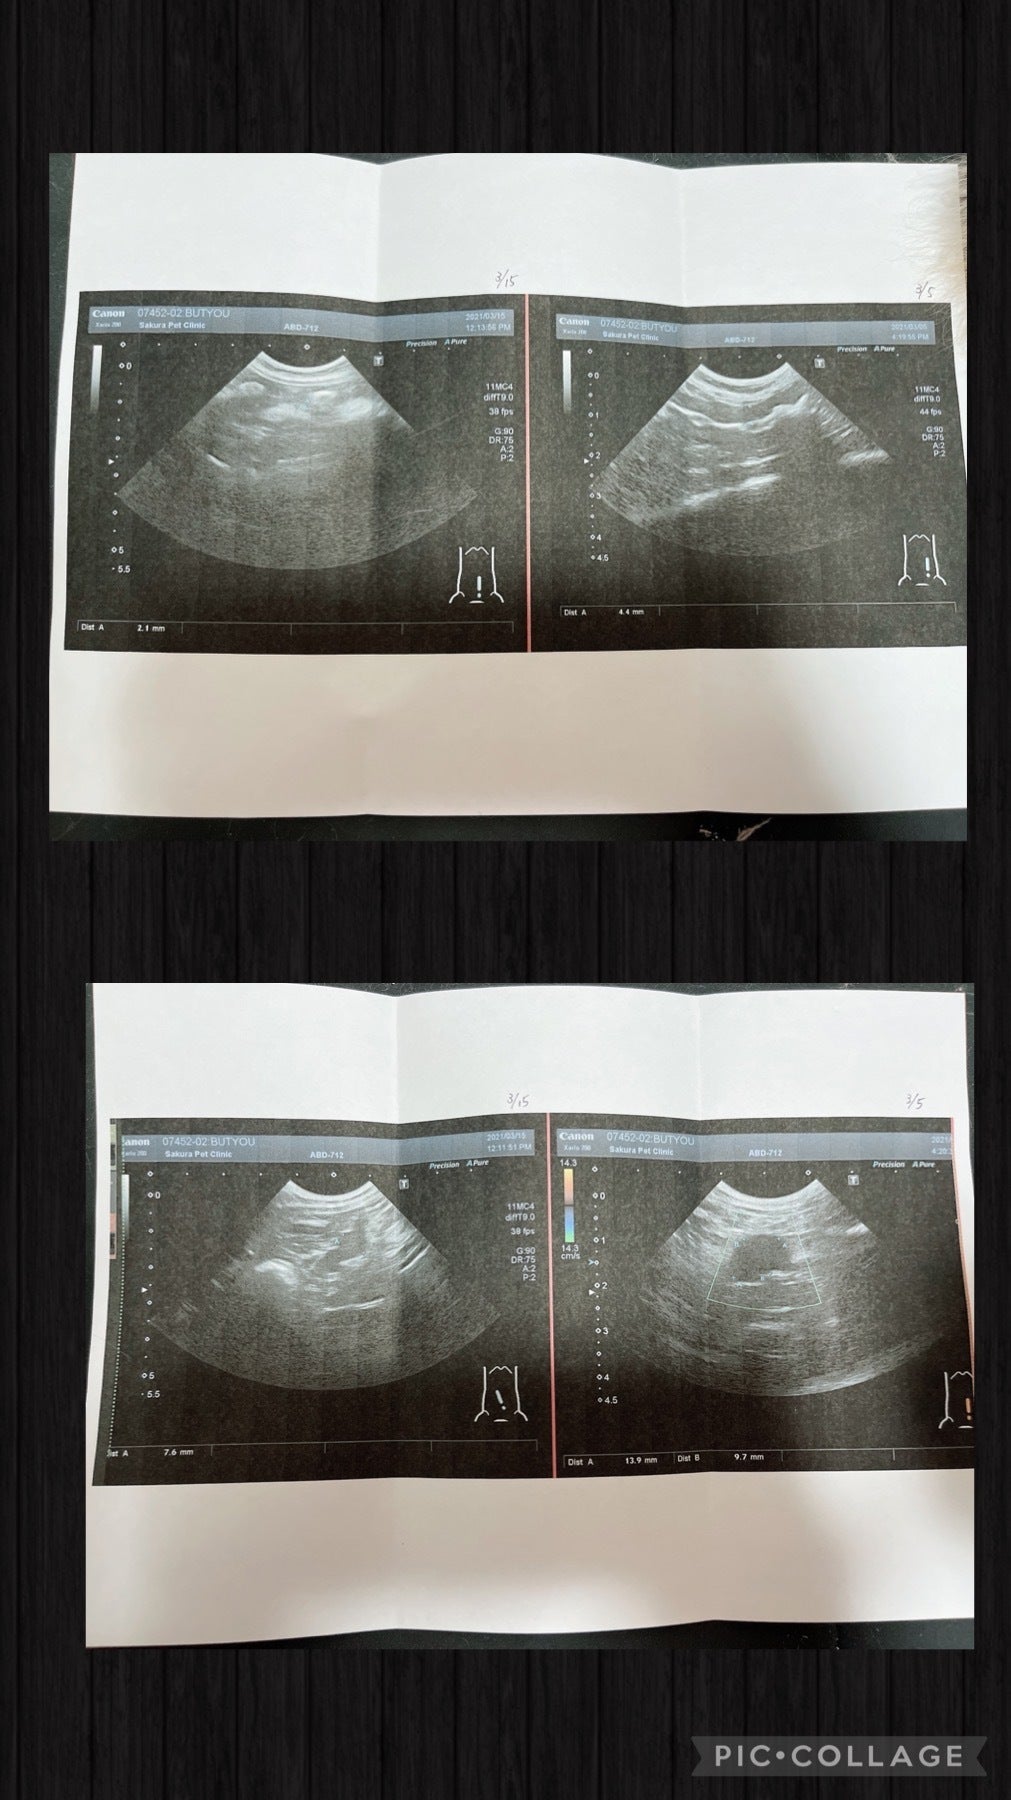

エコーを見てもらうとFIPドライタイプの疑いがあると言われました。

そこでもFIPドライタイプ初見疑いがあると言いわれ、その日はステロイド注射、お薬を処方して貰い帰宅

3月5日部長と協力病院に行きました。

今出来る検査を全てしてもらうと

腸が二倍に腫れて肉芽腫がある

炎症がとても強過ぎる

先生からもFIPドライタイプ初期の疑いが高い

部長ちゃんは検査結果FIPドライタイプが確定し